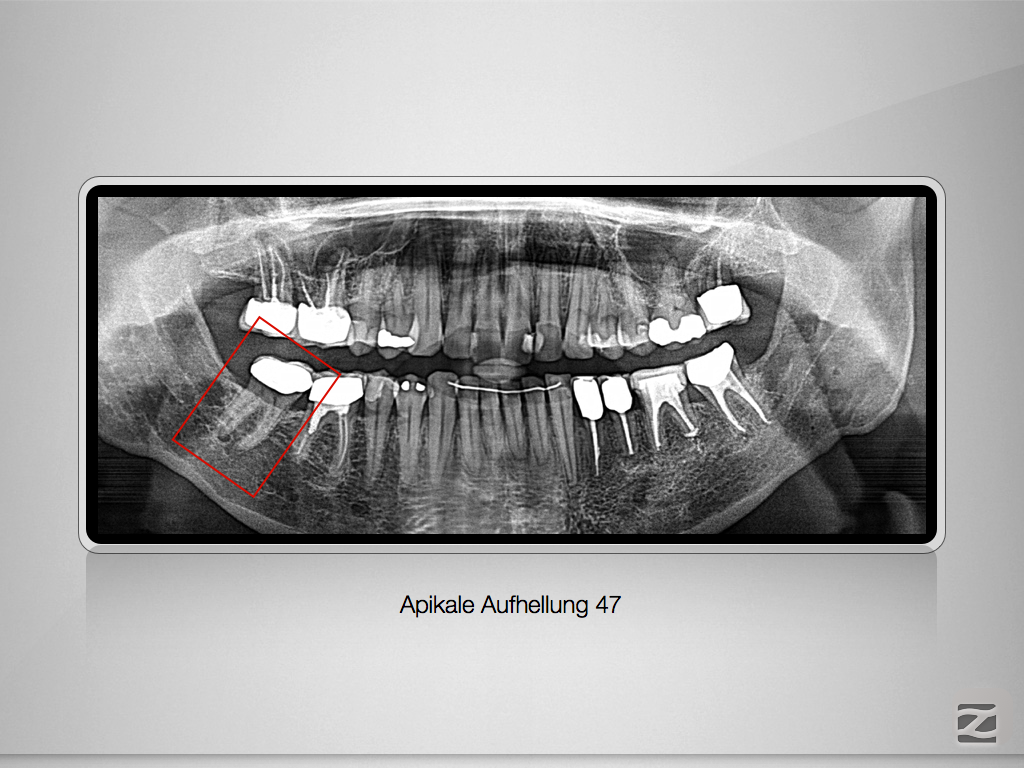

47D.001

Apikale Aufhellung